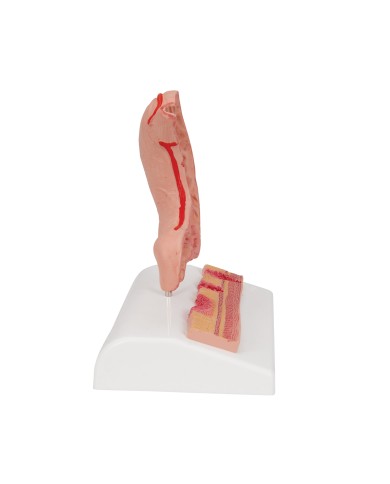

I Modelli anatomici 3B scientific ed Erler Zimmer sono quanto di meglio esista per studiare l'anatomia del corpo umano, il catalogo dei modelli anatomici comprende modelli di cranio, scomponibili, colorati, crani anatomici, crani su cavalletto, e il modello di punta, il cranio in 22 parti, ad incastro magnetico.

Questo e tanto altro ancora trovi nella sezione dedicata ai modellini anatomici, occhi, denti, orecchio, naso e gola, e i modelli anatomici per ostetricia e ginecologia, per lo studio dell'anatomia della pelvi e del bacino umano.

I modelli anatomici didattici sono riproduzioni di strutture anatomiche perfettamente uguali a quelle vere, i modelli di ossa sono realizzati dalla scansione di ossa vere, l'esperienza tattile è assolutamente realistica, ed anche il peso delle ossa corrisponde all'incirca al peso delle ossa vere.

Sono indispensabili per lo studio dell'anatomia umana, oggi è possibile osservare le strutture anatomiche senza la necessità di dissezionare cadaveri o di effettuare studi pericolosi su pazienti vivi.

Gli studenti di medicina utilizzano i modelli anatomici per i loro studi di anatomia umana, studiare l'anatomia sui libri non basta, un modellino anatomico permette uno studio molto più accurato che una foto o un disegno su un libro.